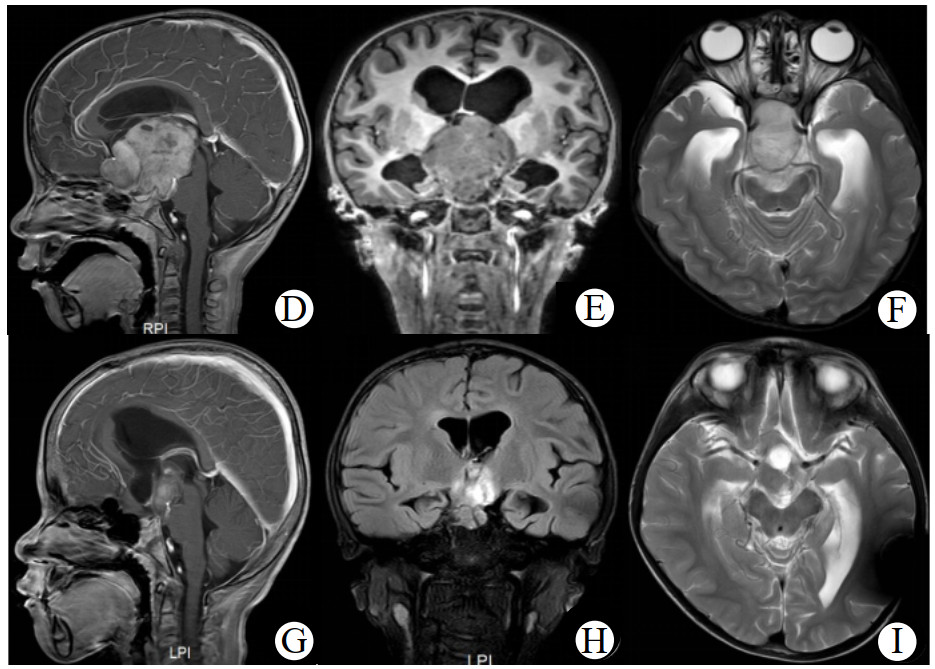

病例1、3、4术后复查肿瘤体积缩小分别为20%、11.7%、42.0%,术后予CV方案化疗,并分别在化疗14个月、8个月、12个月复查较术后肿瘤体积再次缩小10.5%、35%和45.0%。病例2术后拒绝化疗,随访1.5年后复发行2次手术,术后予CV方案化疗结束9个月再次复发,查BRAF基因示KIAA1549-BRAF融合,予靶向药物(曲美替尼片)治疗9个月复查头颅MRI示肿瘤体积较前基本相仿。病例5术后予CV方案联合贝伐珠单抗治疗14个月,化疗结束时复查头颅MRI示肿瘤(2.5 cm×2.4 cm)体积较术后缩小65%,随访25个月复查肿瘤体积(2.8 cm×3.3 cm)较化疗结束时增大54%。其中病例4患儿手术+CV方案治疗后肿瘤体积缩小最明显(图 2)。

| 注:术前(D、E、F)与化疗12月(G、H、I)头颅增强MRI:D、E、F可见鞍上区类圆形混杂团块影(5.3 cm×5.2 cm),肿块稍长T1信号增强后明显强化,囊性T1、T2信号影增强后未见强化,视交叉显示不清,肿块后缘紧贴脑干;G、H、I可见鞍上区肿块较前缩小(2.8 cm×3.5 cm),呈稍长T1稍长T2,内见小囊性长T1长T2信号影,增强后肿块明显强化 图 2 病例4患儿术前及化疗后头颅MRI影像对比 |